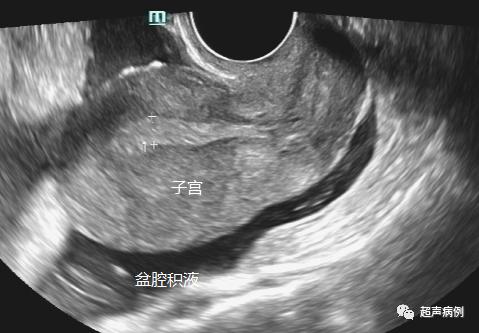

5、排除有无宫外孕等情况。